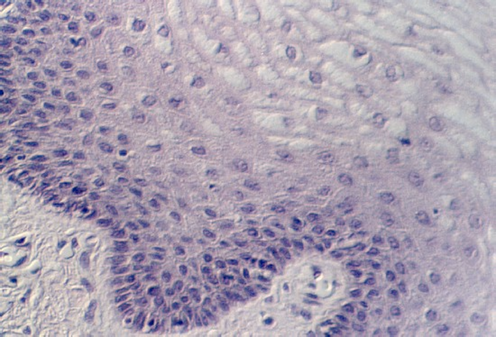

Slide 86 shows a uterus in the proliferative phase. The endometrium is illustrated in the photograph below. Note that the cells are low columnar to high columnar. The glands are relatively straight with a narrow lumina. Outside the glands is the highly cellular lamina propria. The following photos illustrate the proliferative phase with higher magnifications.

Moving toward the vagina, one can see the abrupt transition between the cervical glands and the stratified squamous epithelium of the vagina. The region showing the vaginal and cervical areas juxtaposed is seen in the following photo.

A low magnification view of the vagina is shown in this photograph. The epithelium is stratified squamous. Underneath the epithelium is a lamina propria. Note that there is no muscularis mucosa. You will use this feature to distinguish the vagina from the esophagus. Another difference is the fact that the vagina has some tight junctions which, along with a lipid secretory material, make the epithelium a permeability barrier.